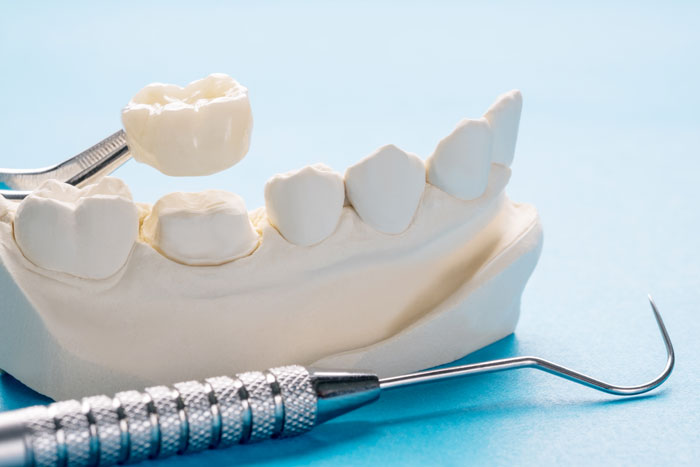

Dental Crowns

Dental x-rays are essential preventative diagnostic tools that provide valuable information not otherwise visible during a dental exam. Dentists and dental hygienists use this information to safely and accurately detect hidden dental abnormalities and create an appropriate treatment plan. Without x-rays, problem areas may go undetected.

Crowns for teeth restoration

The standard restoration for a tooth with damage that can no longer be repaired that is broken, discolored, badly shaped or has too much decay for a dental filling is a dental crown that completely covers the prepared tooth. The crown is fitted over the original tooth after any decay has been removed. Flat Rate Dental specializes in crowns and will give you a beautiful restoration that will look, feel and look like your natural teeth.

We offer the latest technology in crowns

Space age technology has revolutionized the modern cosmetic crown. State-of-the-art materials and manufacturing techniques now provide new metal-free, all-ceramic crowns that are so life-like, only your dentist will know. In addition, to their dramatically improved aesthetics, not all ceramic crowns match or exceed the strength of traditional restorations. They also eliminate sensitivity to heat and cold as well as allergic reactions.

Full Porcelain Crown

Porcelain crowns made in a nearby dental lab is attractive, strong, stable, and highly resistant to wear. It offers a high level of biocompatibility because it does not contain metal.

A porcelain crown provides the best natural color match to the rest of your teeth and is an excellent choice for front teeth. The aesthetic quality of a porcelain crown is your best option for a crown. Some offices will suggest a Cerec crown, but we do not advise this in-office option as the crown is not as strong and typically does not last as long.